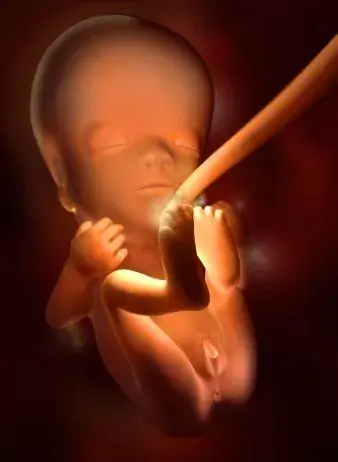

孕早期胎兒發育的過程及B超所見妊娠是一個復雜的過程,卵子受精后,進入宮腔,胚胎及附屬物迅速生長發育直至成熟的過程中,每個孕周都會有不同的變化。

4周:

胎兒只有0.2厘米。受精卵剛完成著床,羊膜腔才形成,體積很小。超聲還看不清妊娠跡象。

5周:

胎兒長到0.4厘米,進入了胚胎期,羊膜腔擴大,原始心血管出現,可有搏動。B超可看見小胎囊,胎囊約占宮腔不到1/4,或可見胎芽。它蘋果籽一樣大小,外觀像個“小海馬”。

6周:

胎兒長到0.85厘米,胎兒頭部、腦泡、額面器官、呼吸、消化、神經等器官分化,B超胎囊清晰可見,并見胎芽及胎心跳。

7周:

胎兒長到1.33厘米,胚胎已具有人雛形,體節已全部分化,四肢分出,各系統進一步發育。B超清楚看到胎芽及胎心跳,胎囊約占宮腔的l/3。此時還聽不到胎心音,但胚胎的心臟已經劃分成左心房和右心室,每分鐘大約跳150下。

8周:

胎兒長到1.66厘米,胎形已定,可分出胎頭、體及四肢,胎頭大于軀干。B超可見胎囊約占官腔1/2,胎兒形態及胎動清楚可見,并可看見卵黃囊。器官已有明顯的特征,手指和腳趾間有少量的蹼狀物。胚胎的各種復雜的器官都開始成長,牙和腭開始發育,耳朵在繼續成形,胎兒的皮膚很薄,血管清晰可見。胚胎開始有運動。

9周:

胎兒長到2.15厘米,胎兒頭大于胎體,各部表現更清晰,頭顱開始鈣化、胎盤開始發育。B超可見胎囊幾乎占滿宮腔,胎兒輪廓更清晰,胎盤開始出現。胎兒所有的器官、肌肉、神經都開始工作,并且發育迅速。手部從手腕開始變得稍微有些彎曲,雙腳開始擺脫蹼狀的外表,眼簾開始覆蓋住眼睛。

10周:

胎兒長到2.83厘米,胎兒各器官均已形成,胎盤雛形形成。B超可見胎囊開始消失,月芽形胎盤可見,胎兒活躍在羊水中 。形狀及大小像一個扁豆莢。胎兒的眼皮開始粘合在一起,直到27周以后才能完全睜開。手腳發育完成,手指和腳趾清晰可見,手臂更長而且肘部變得更加彎曲。胎兒的耳朵發育已經完成。

11周:

胎兒長到3.62厘米,胎兒各器官進一步發育,胎盤發育。B超可見胎囊完全消失,胎盤清晰可見。胎兒開始能做吸吮、吞咽和踢腿動作,胎兒的手指甲和絨毛狀的頭發等細微之處已經開始發育,維持胎兒生命的器官如肝臟、腎、腸、大腦以及呼吸器官也已開始工作。

12周:

胎兒長到4.58厘米,外生殖器初步發育,如有畸形可以表現,頭顱鈣化更趨完善。顱骨光環清楚,可測雙頂徑,明顯的畸形可以診斷,此后各臟器趨向完善。手指和腳趾已經完全分開,部分骨骼開始變得堅硬,并出現關節雛形。